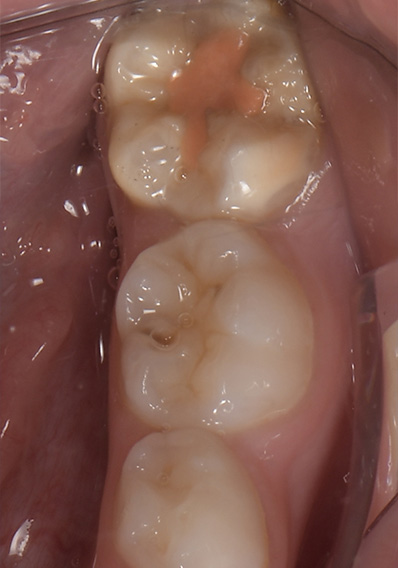

Fig. 04 : scellement de sillon au CVI (triage rose) ayant permis d’attendre l’éruption complète (sans atteinte carieuse, contrairement à la 5 présentant une atteinte occlusale).